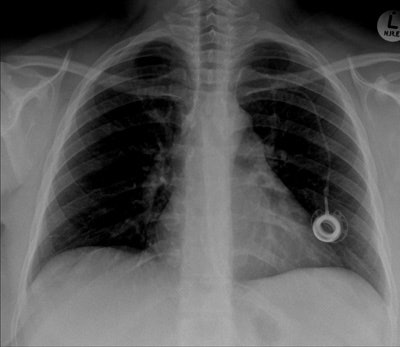

The postoperative radiograph showed no residual fragments.

Postoperative chest radiograph.Discussion